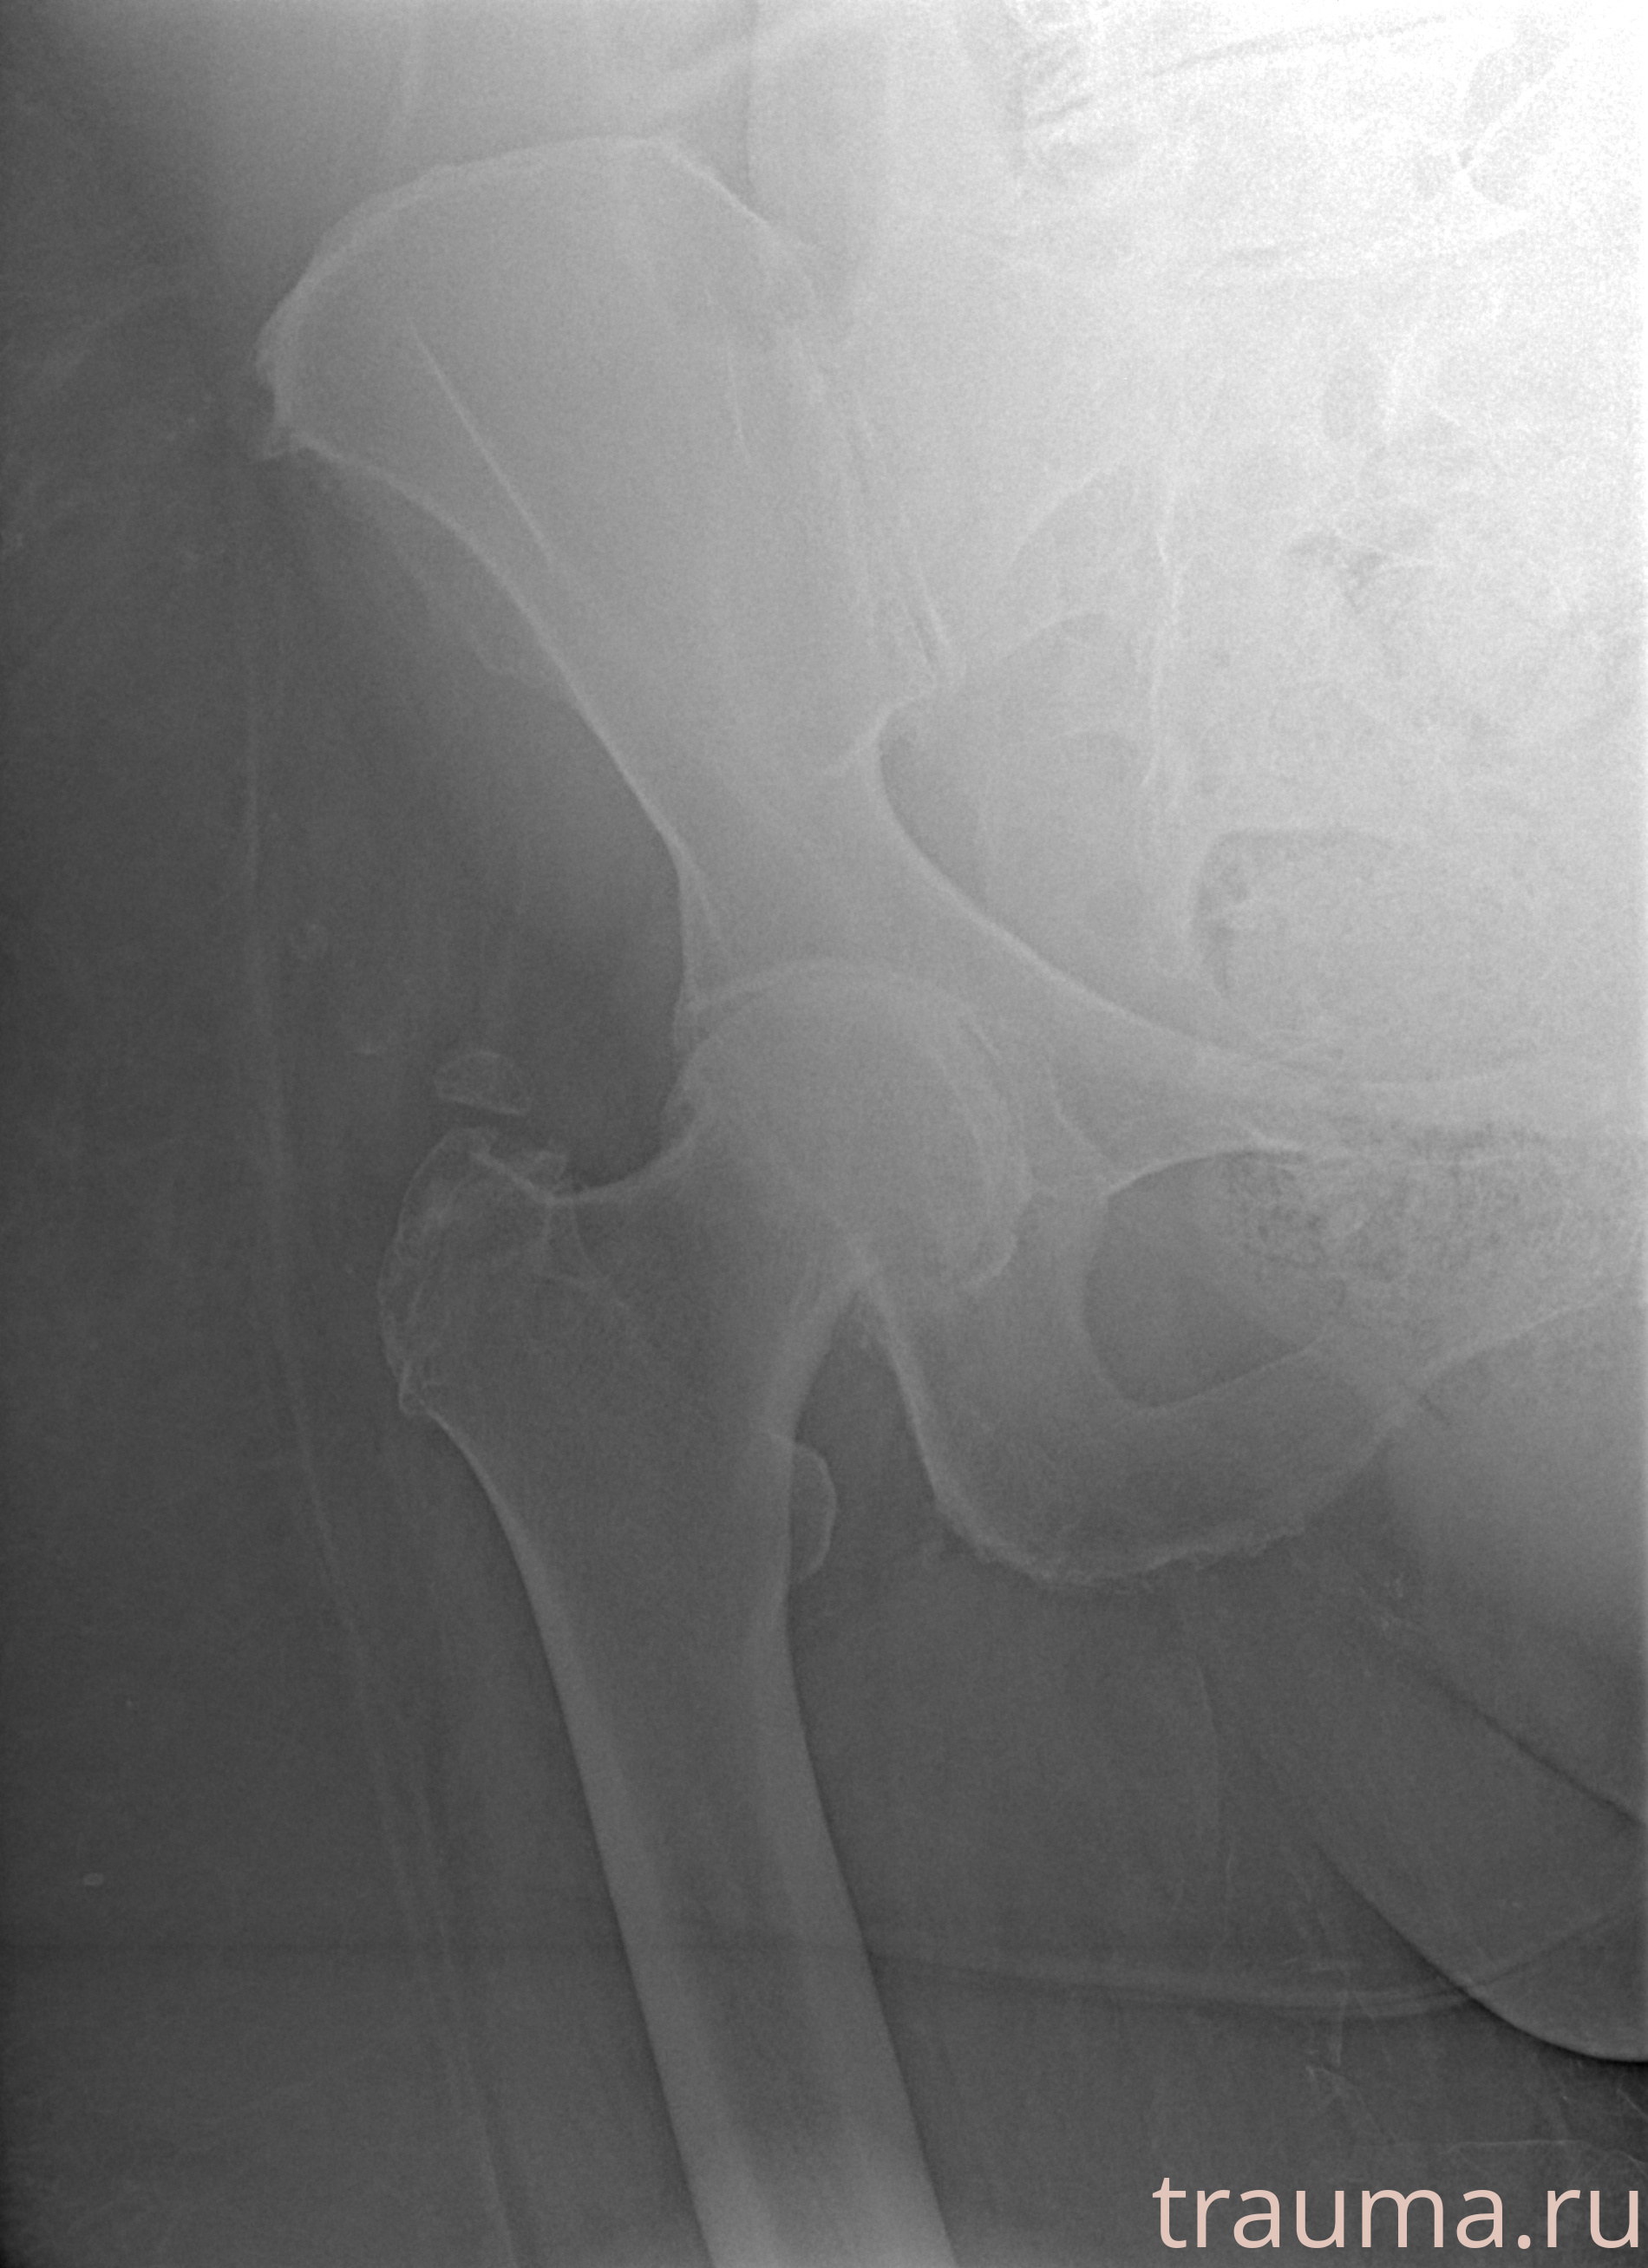

Рентгенограммы

Рентген на дому: по вашему адресу приезжает врач-рентгенолог, травматолог-ортопед с мобильным рентгеновским аппаратом, проводит диагностику травмы или заболевания, делает необходимые рентгенограммы, дает рекомендации по дальнейшему лечению. Получить качественные снимки в домашних условиях возможно благодаря уникальной методике, разработанной МосРентген Центром для института  Склифосовского